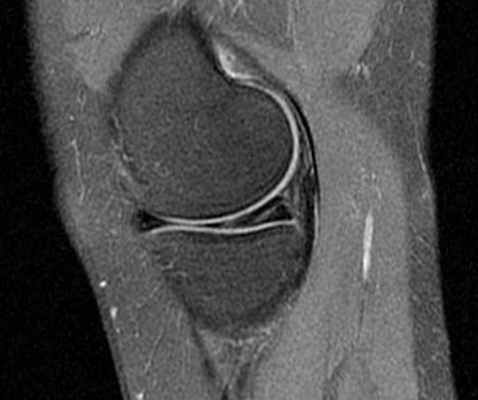

МРТ коленного сустава. Т2-взвешенная сагиттальная МРТ. Медиальный мениск в норме.

Медиальный мениск (ММ) больше латерального (ЛМ), имеет форму лунного серпа, занимает около 50% суставной поверхности медиального отдела сустава. Задний рог ММ толще заднего рога ЛМ. В ширину ММ от 6 мм в области переднего рога до 12 мм в области заднего рога. Поперечная (межменисковая) связка соединяет передние рога ММ и ЛМ. У 40% людей она отсутствует, что видно при МРТ коленного сустава.

Важнейшую функцию амортизации (поглощения и перераспределения нагрузки), обеспечение стабильности, а также смазку и питание сустава выполняет мениск. Повреждения менисков чаще всего наблюдаются у спортсменов. Мениск представляет собой С-образную фиброзно-хрящевую структуру, прикреплённую к мыщелковым поверхностям большеберцовой кости. Концы «С» направлены к центру, верхняя поверхность мениска вогнутая, что улучшает контакт с головкой бедренной кости. Нижняя поверхность мениска плоская. При МРТ коленного сустава в сагиттальной плоскости видно, что наружная часть мениска выпуклая и толще центральной. Толстая внешняя часть мениска даёт возможность плотного его прилегания к суставной капсуле. У детей мениск имеет сосуды. Большая часть мениска у взрослых бессосудистое образование и только самая периферическая часть имеет сосуды. Высота мениска в норме 3-5 мм. Делится мениск на передний рог, тело и задний рог.